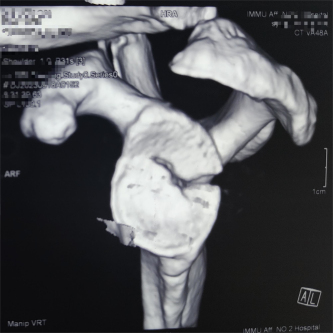

(术中影像)

患者因交通事故致伤导致左肩关节盂骨折及左肩锁关节脱位和右尺桡骨骨折,骨折移位明显,疼痛剧烈,具备手术指征。但患者为75岁高龄,基础疾病多,担心患者无法耐受过大的手术创伤。经术前讨论,创伤外科中心张立峰教授团队决定为患者应用骨科手术机器人辅助经皮内固定治疗肩关节盂骨折的手术方案。术中,通过机器人进行采集数据、并规划手术等人工智能操作,仅用1cm切口即成功完成手术。

“天玑”Ⅱ骨科手术机器人用于辅助医生精确定位植入物或手术器械,可广泛应用于骨科手术,其临床精度可达1mm以内。自2021年91直播 成功引进后,已完成各类骨科手术。本次应用骨科机器人进行肩关节盂骨折手术治疗,进一步拓展了“天玑”II骨科机器人的诊疗范围,完美呈现了“人机结合”,更为创伤急救中心的创新治疗带来新思路。创伤外科中心将继续充分利用骨科机器人的技术优势在新的领域开展临床治疗,提高自治区创伤救治水平,更好地造福患者。